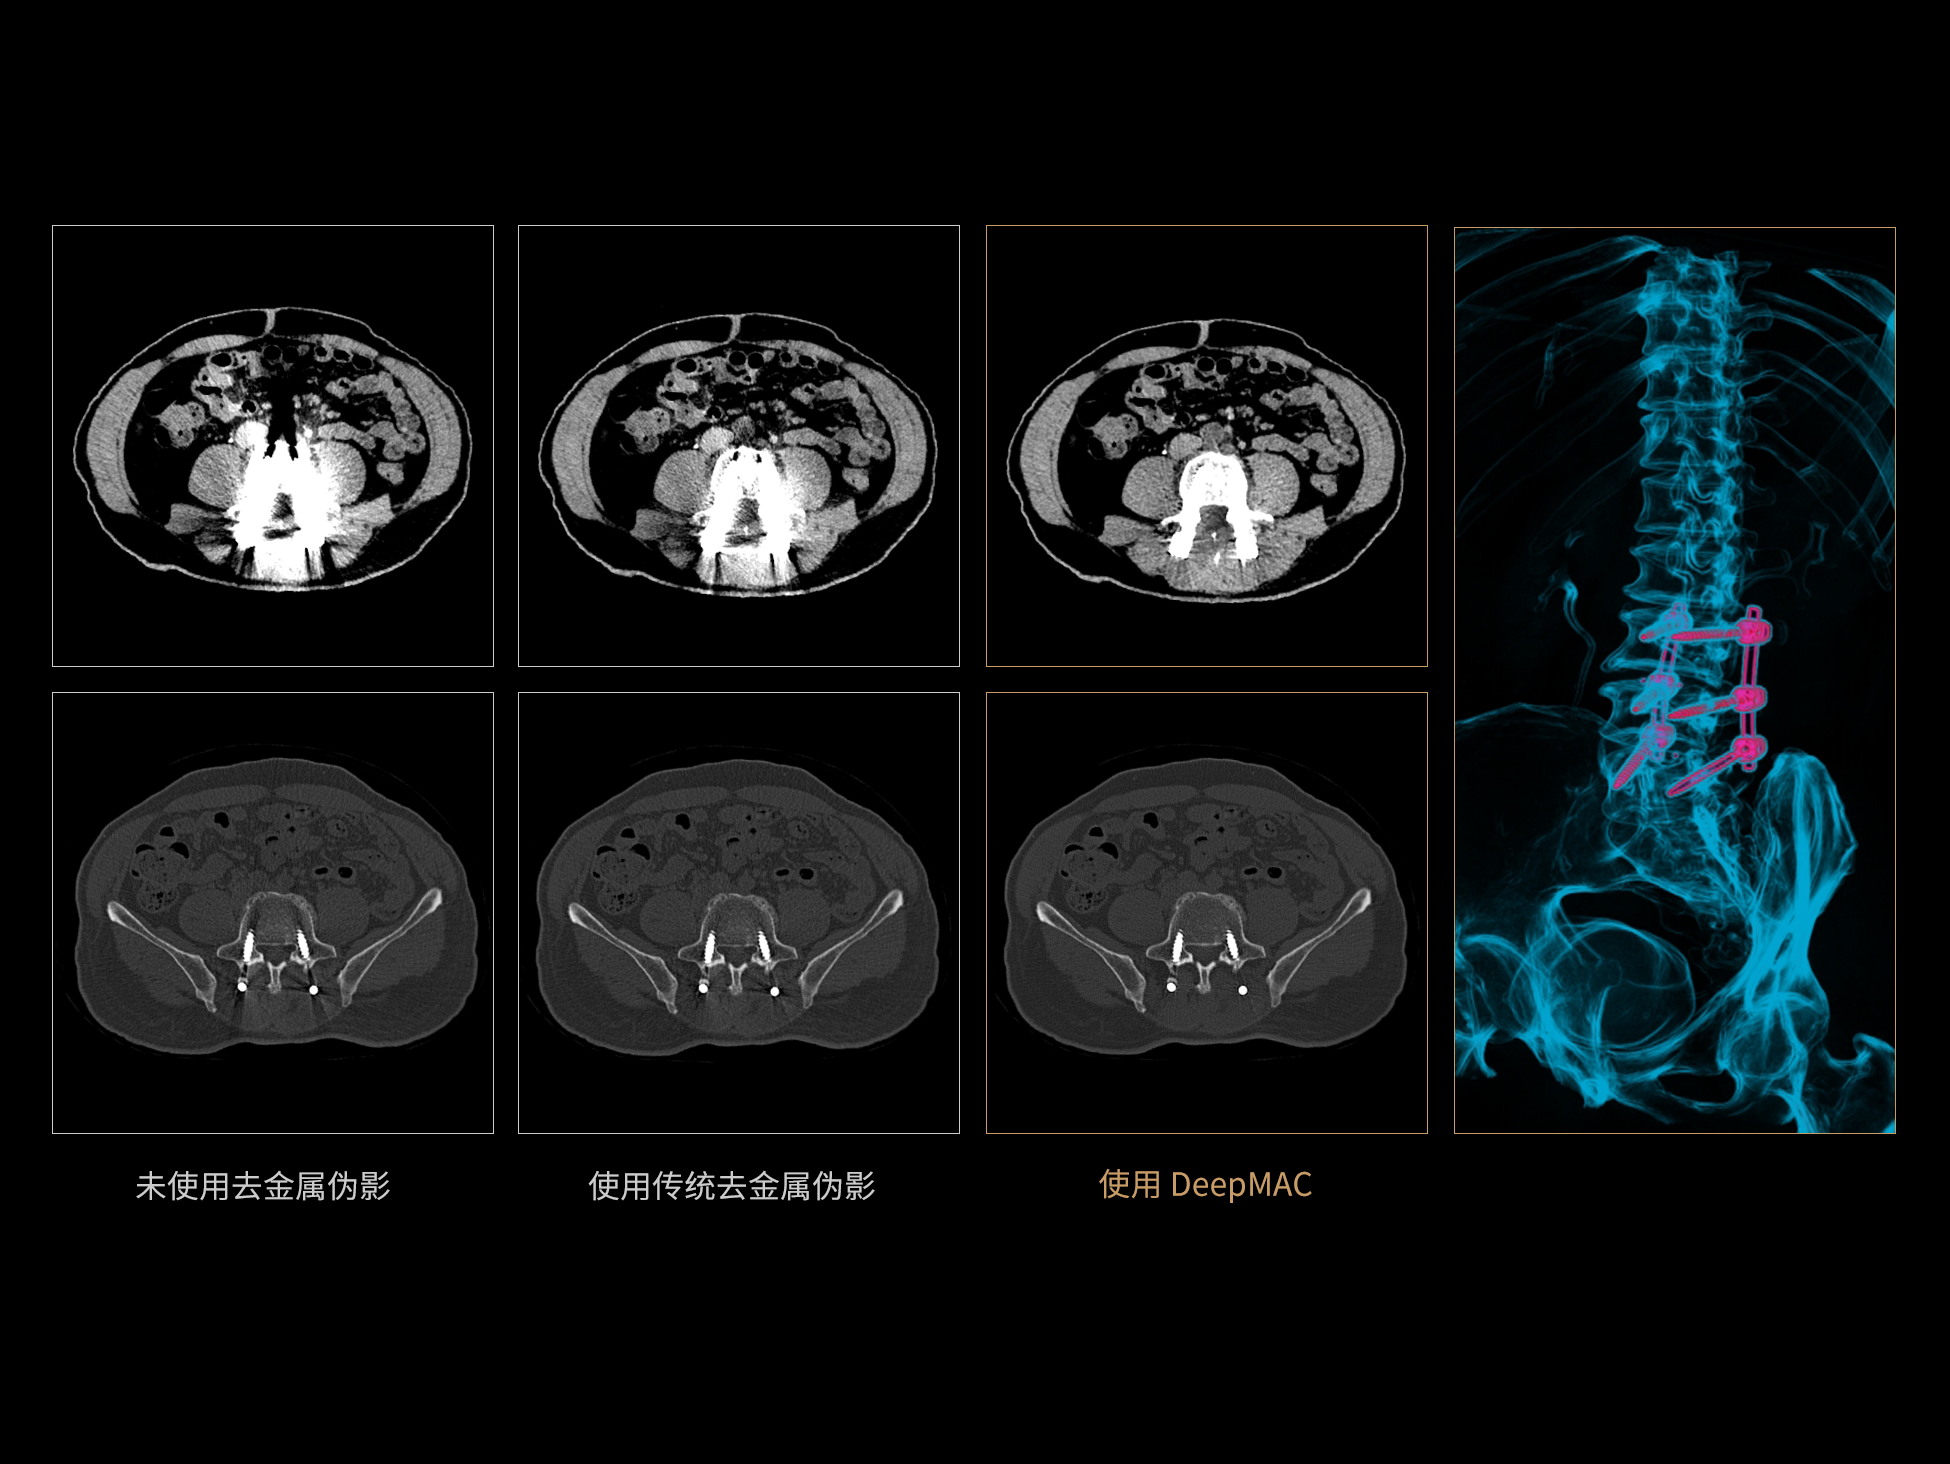

uCT 868 搭载联影最新一代 uSense 人工智能平台,将智能化深度融入 CT 扫描全流程,从感知细微生理运动到精细结构探测,再到多场景诊疗优化。以 AI 为核心驱动力,uSense 重塑成像各环节,打造高效、高清的智慧扫查体验。在心脏成像领域,uSense 结合宽体探测器、心脏专研AI重建算法与AI冠脉运动追焦技术,在保持低剂量的同时,有效抑制运动伪影,精准呈现软斑块、混合型斑块及支架细节,助力冠脉成像惠及更多患者。针对多科室疾病临床应用场景,uSense 平台提供全方位的智能解决方案:包括头部运动伪影智能校正、金属植入物伪影抑制、扫描视野扩展等先进算法。这些创新技术使 uCT 868 能够构建覆盖全场景的智能诊疗体系,持续拓展 AI 赋能医学影像的边界。